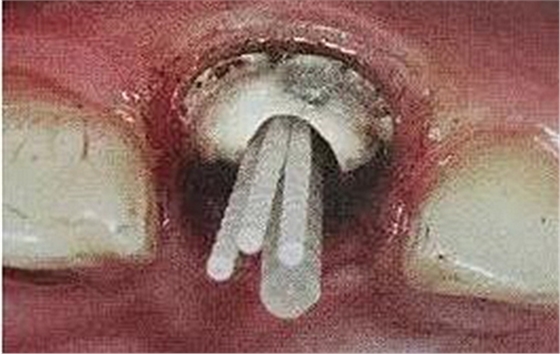

如果是后牙需要打多個纖維樁時要檢查是否互相妨礙以及就位順序等。

一般纖維樁使用數(shù)目要根據(jù)根管的粗細(xì)和牙體缺損范圍來設(shè)計,像牙膠尖根充一樣,在主尖周圍可以放置輔尖。

后牙一般按照牙體缺損范圍來設(shè)計,一般2到4個足夠了。

在操作的過程中要注意無菌操作,保證纖維樁的無菌狀態(tài)。推薦將樹脂核堆好之后再截斷纖維樁,而不是截斷后再粘接。如下圖: